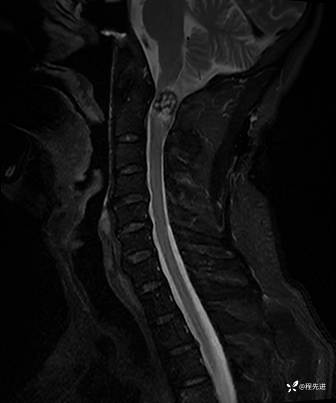

T1增强: